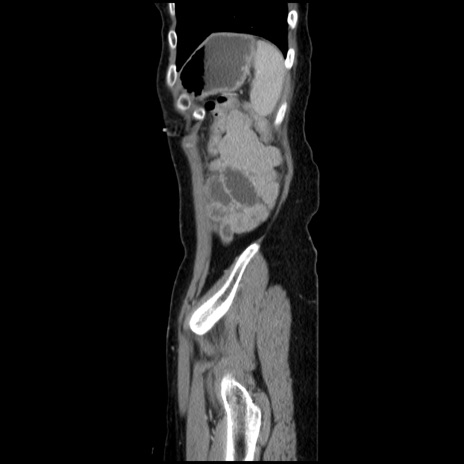

症例32(矢状断像)

【症例】40歳代 女性

【主訴】上腹部痛、嘔気・嘔吐

【現病歴】約9時間前頃から急に上腹部痛、嘔気、嘔吐が出現。改善しないため救急要請。

【既往歴】子宮頚癌(広汎子宮全摘術、放射線療法)、腸閉塞

【身体所見】腹部:平坦、軟、腸雑音亢進、上腹部を中心に腹部全体に圧痛あり。

【データ】WBC 8400、CRP 0.03